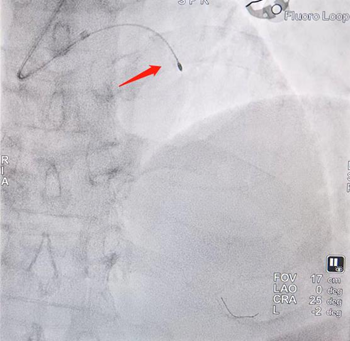

冠脉造影提示左主干至前降支近段重度狭窄,且全程可见明显钙化影。洪浪、尹秋林团队应用冠脉腔内影像学技术-OCT对该血管进行了进一步的评估,结果显示:左主干至前降支近段全程可见环形钙化,最严重处位于左主干末端,此种情况极易造成支架膨胀不全。团队先使用冠脉内旋磨术对冠脉钙化病变进行旋磨,然后使用冲击波球囊对钙化病变进行处理。结果显示严重钙化处出现钙化断裂,提示支架植入后可以获得满意的支架膨胀效果。

发射脉冲震波球囊膨胀过程

Shockwave球囊治疗后